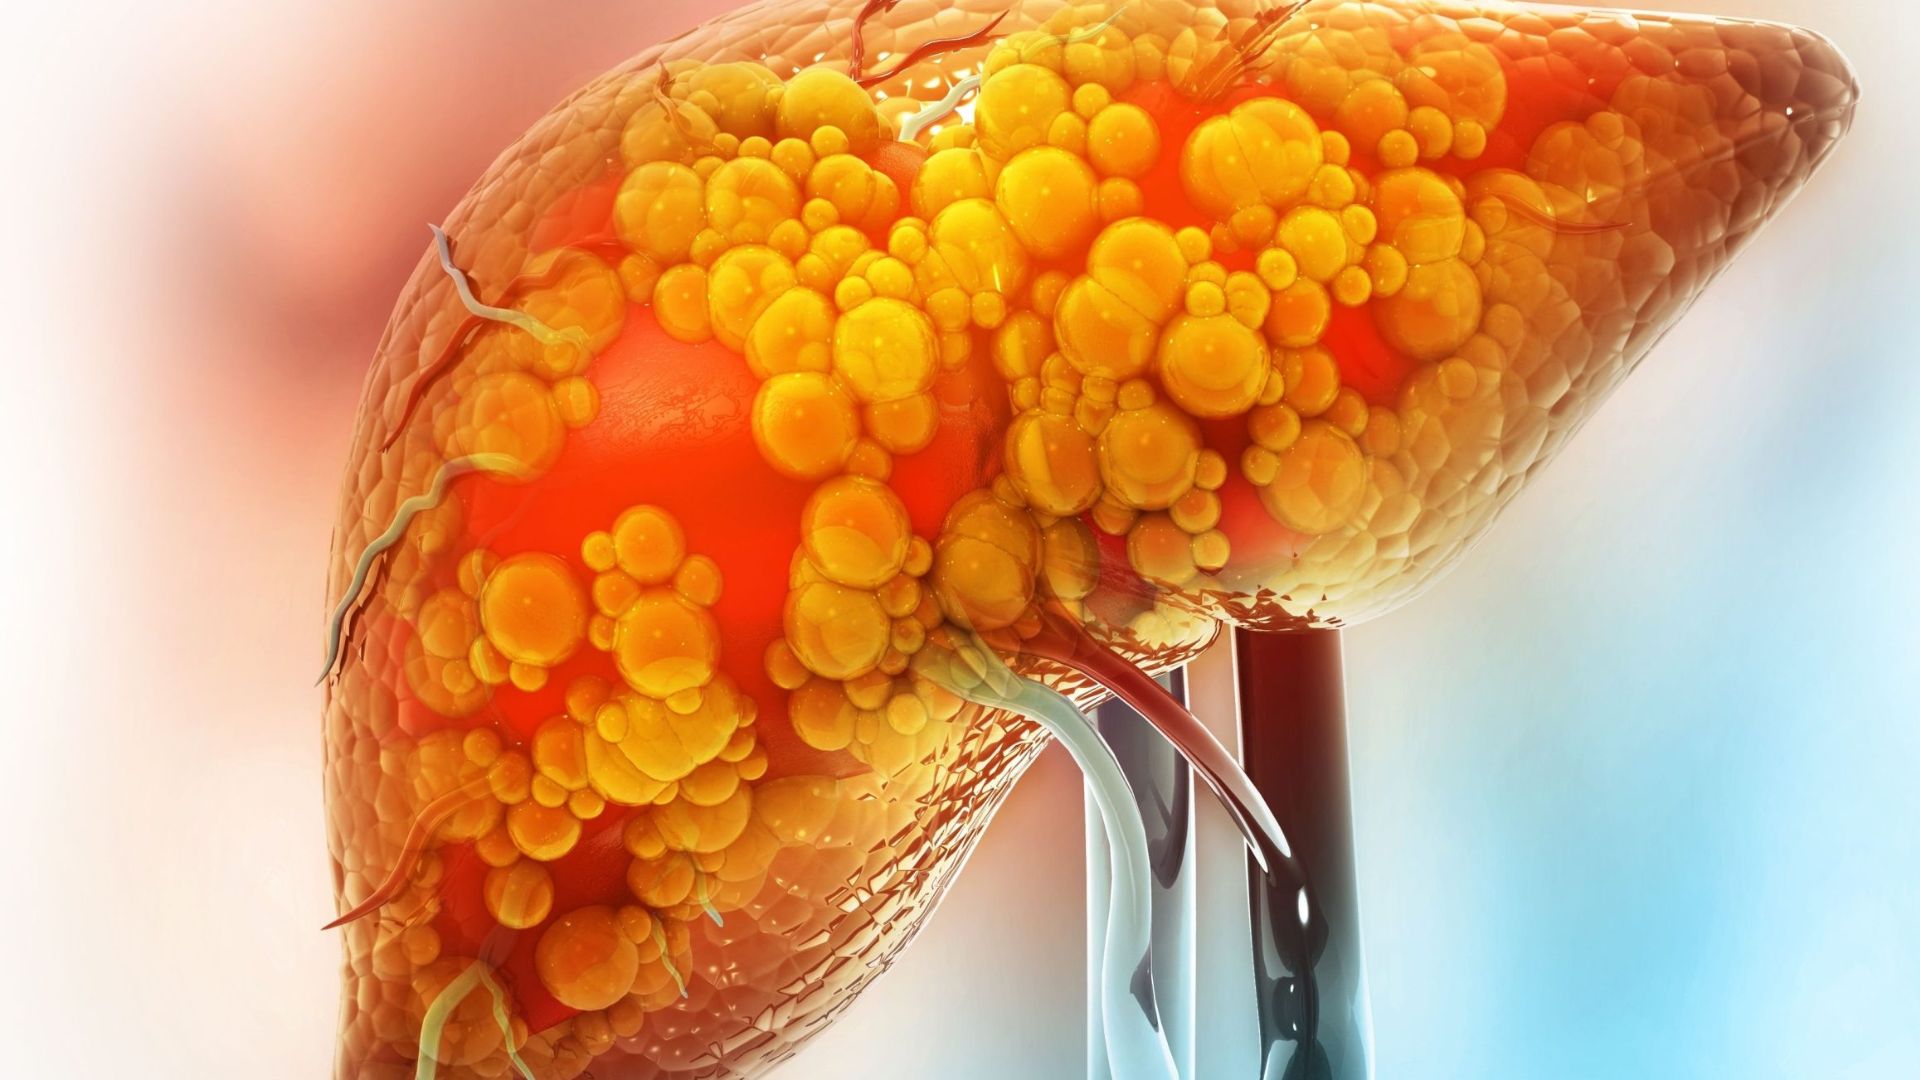

Gan nhiễm mỡ là tình trạng tích tụ chất béo trong gan. Có 2 dạng chính gồm:

Gan nhiễm mỡ không do rượu (NAFLD): Tích tụ mỡ không liên quan đến việc uống nhiều rượu

Gan nhiễm mỡ do rượu (AFLD): Tích tụ mỡ liên quan đến việc tiêu thụ nhiều rượu

NAFLD xảy ra ở tới 90% người béo phì. Tình trạng này có thể tiến triển thành một dạng nghiêm trọng hơn gọi là viêm gan nhiễm mỡ không do rượu (NASH), liên quan đến viêm và tổn thương gan.

Sự tích tụ mỡ trong gan có thể ảnh hưởng đến khả năng tự bảo vệ của gan trước các chất độc đi từ ruột đến gan thông qua tĩnh mạch cửa. Những chất này có thể gây viêm gan, dẫn đến hình thành sẹo.